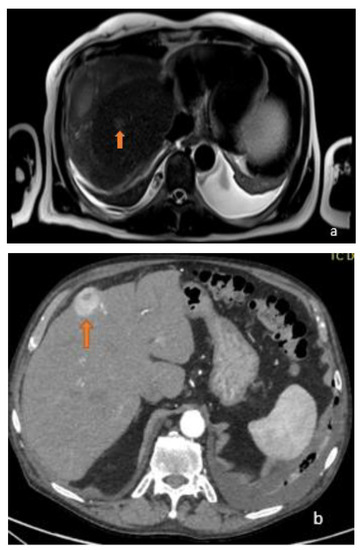

3.1. FLL Feature Characteristic

5.1. FLL Feature Characteristic

6. Benign MRI Features